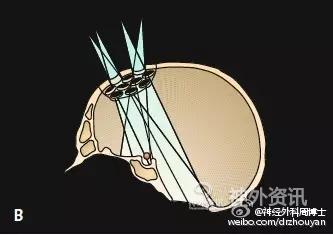

图示额颞开颅-额下入路的发展历程。注意观察皮肤切口和骨瓣大小的变化。A. Dandy的额颞入路;B. Yasargil的翼点入路(应用显微外科技术);C. 眶上keyhole开颅入路:显露Yasargil翼点入路的额底部分,显著缩小了开颅范围,也显著降低了颅内、外的手术创伤。

A. 标准的大范围开颅,暴露术野深部病变的视角呈漏斗型; B. 这种传统的大范围开颅方法可以被视为若干keyhole手术入路的整合;C. 只要选择正确的小骨窗路径,手术视角呈扇形扩大。路径越短,手术视角越窄;而路径越长(术野深部病变),手术视角则越宽。这种路径选择方法,有时还可同时处理对侧的病变。